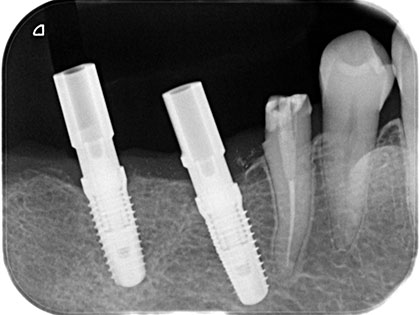

左下奥歯6、7番目にインプラント治療を行った症例

左下が腫れたり、噛むと痛いとの事で来院され、インプラント治療を希望された患者様の症例になります